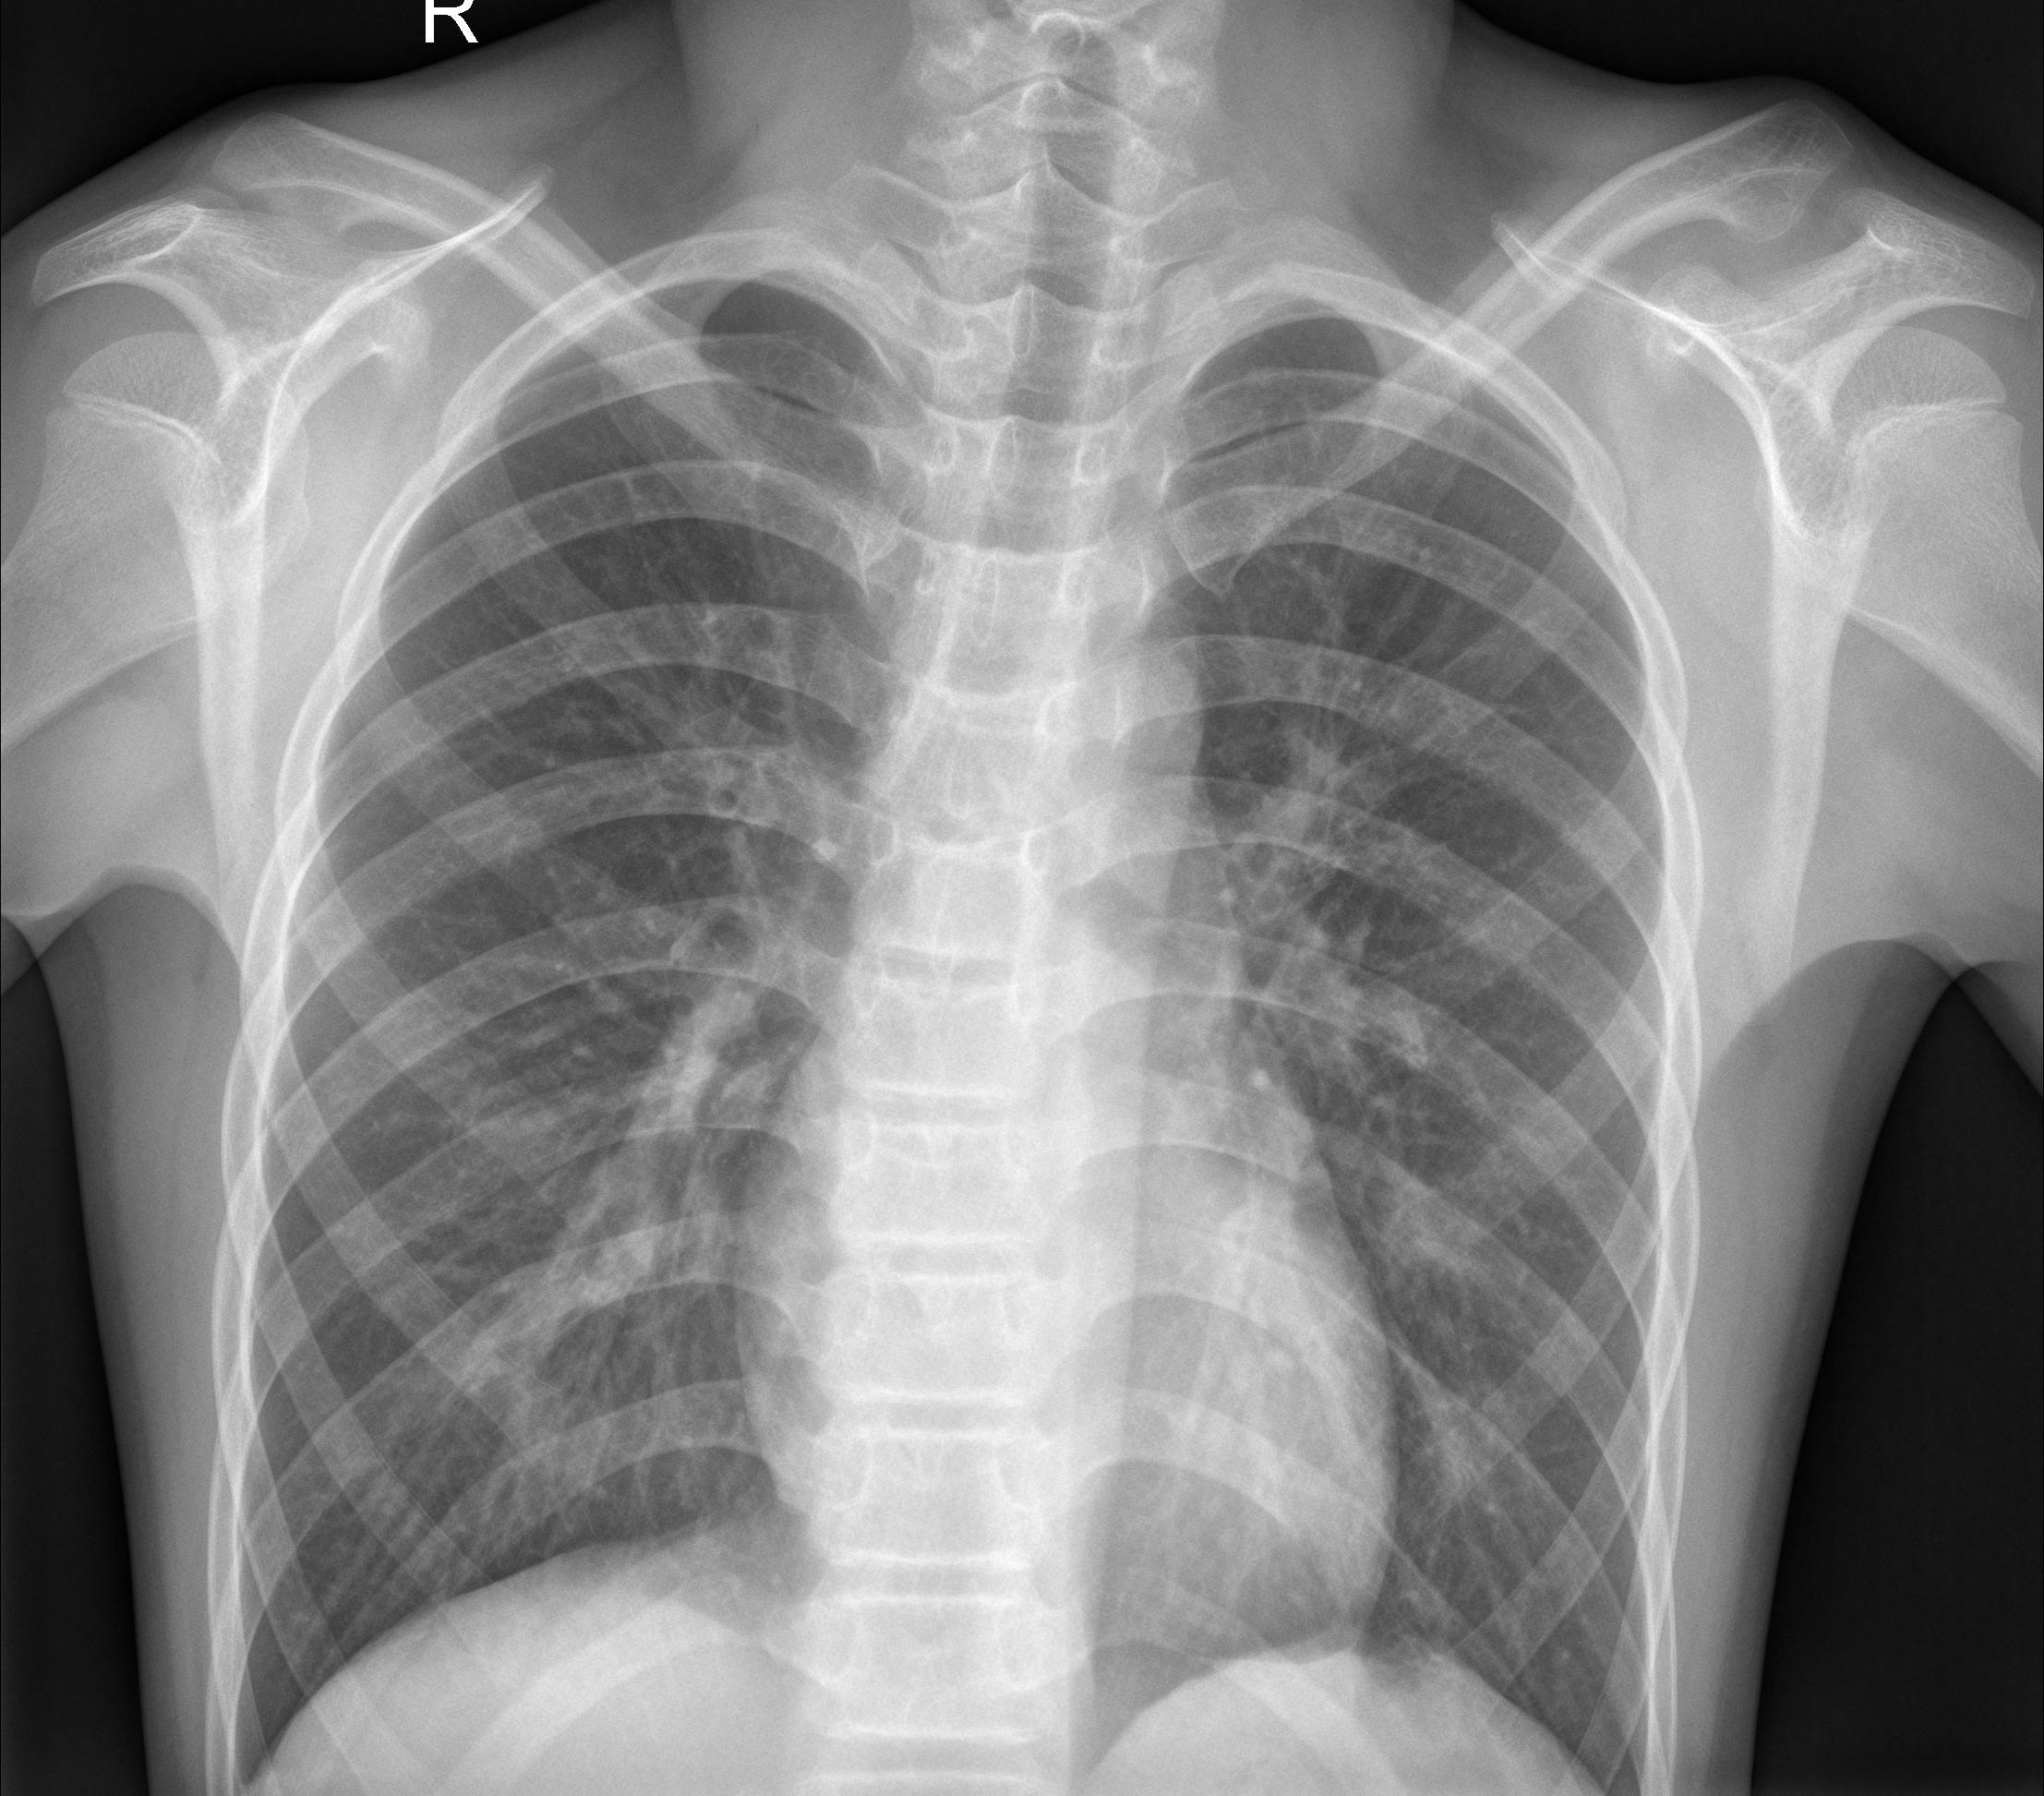

如下图为随机的两张正常的X射线图片